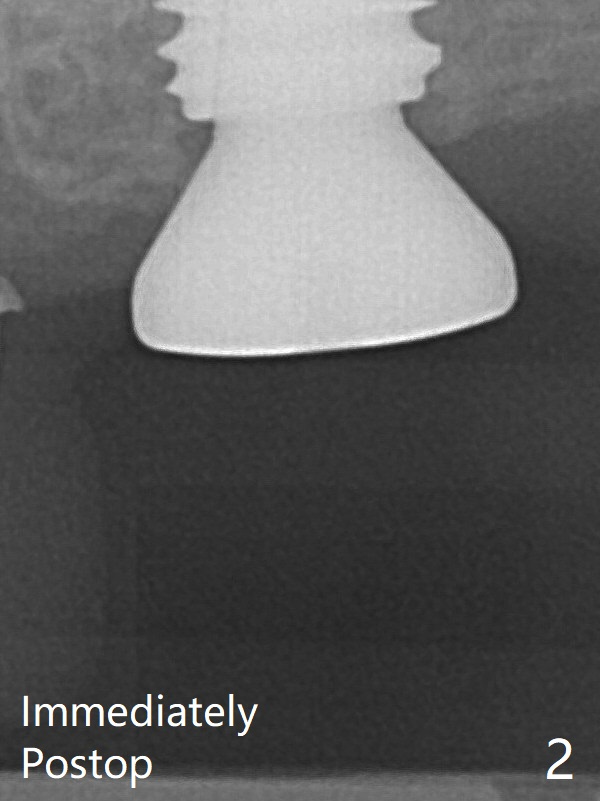

Implant placement at #14 (Fig.2 (bitewing)) with guide.  There is no gross bone loss 5 months postop (Fig7).